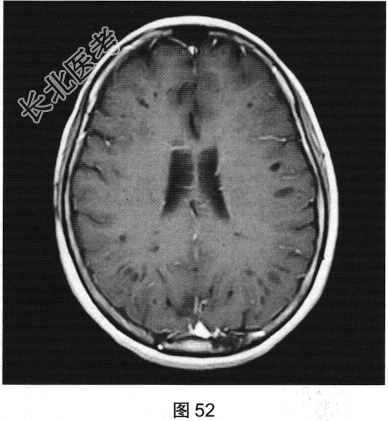

- [材料题] 患者女性,56岁,诉头痛、头晕多年,要求行颅脑MRI检查。查体:神志清楚,问答切题,查体合作。双眼睑无水肿、下垂及闭合不全,双侧瞳孔直径约3.0mm,直接、间接反射均灵敏。双眼视力视野粗侧无异常。发音清晰无嘶哑。耸肩及转头力量对称。四肢活动灵活,肌力、肌张力正常,深浅感觉基本正常;病理征阴性。患者行颅脑MRI检查,如图41~图44所示。

- 多项选择题2.[提示]患者行FLAIR、DWI及增强扫描,见图45~图54。该患者MRI影像的主要阳性表现有( )

C、双侧放射冠及半卵圆中心多发条状、圆形及卵圆形异常信号灶

E、病灶呈长T1、长T2信号,FLAIR为低信号,DWI为低信号,ADC为高信号

F、病灶呈长T1、长T2信号,FLAIR为稍高信号,DWI为低信号,ADC为高信号